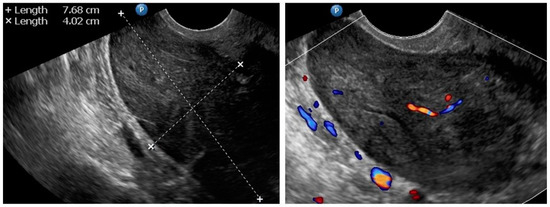

| 3 (37) | Atypical uterine lesion | Figure A3 | Yes | No | Lipoleiomyoma (UG-TUC core needle biopsy) | No | - | Yes | Yes |

| 4 (56) | Atypical uterine lesion | Figure A4 | Yes | Yes | Leiomyoma (transvaginal ultrasound guided core needle biopsy) | Yes | Leiomyoma and adenomyosis | Yes | No |

| 5 (50) | Atypical uterine lesion (metastatic adenocarcinoma G3 in inguinal lymph node) | Figure A5 | Yes | No | Leiomyoma (UG-TUC core needle biopsy) | No | Uterus / tumor not resected because primary urological carcinoma was diagnosed | Yes | Yes |

| 6 (38) | Atypical uterine lesion | Figure A6 | Yes | No | Leiomyoma, epithelioid variant (UG-TUC core needle biopsy) | Yes (lesion enlarged during follow-up) | Leiomyoma, epithelioid variant | Yes | Yes |